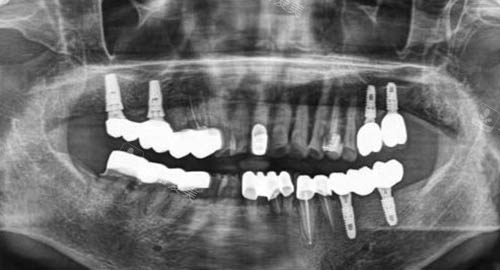

多颗牙齿种植ct

种牙方面,医生会根据患者的具体情况制定个性化的种植方案,手法轻柔且比较准,能够有效减少患者的痛苦,提高种植成功概率。

许多患者在种牙后都表示结果非常好,牙齿的咀嚼功能得到了很不错的修复。